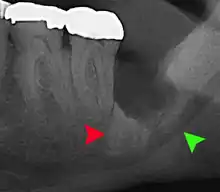

Impacted wisdom tooth with a backward tilt (distoangular impaction) and chronic infection to back of crown (green arrow)